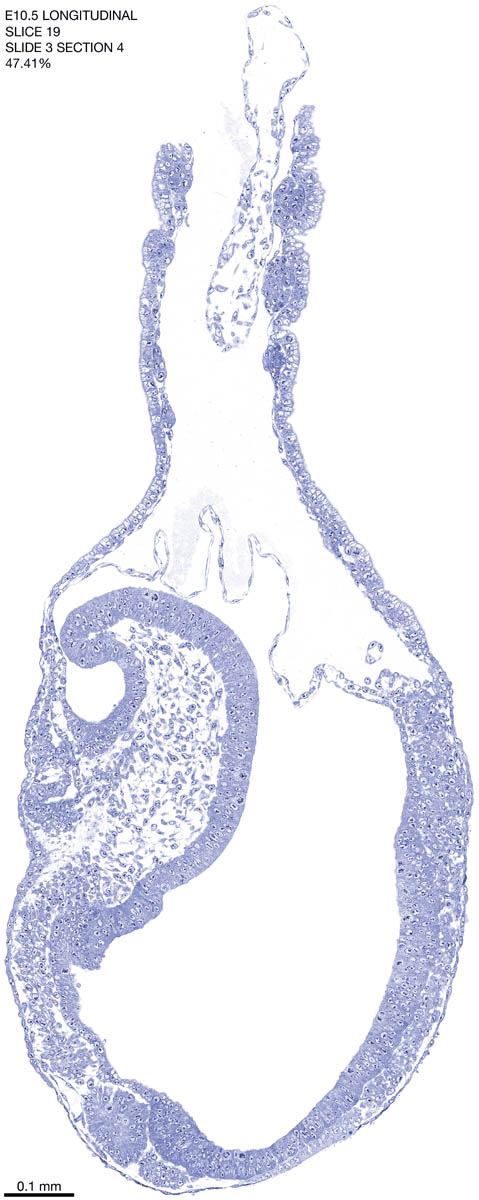

E10.5 Longitudianal Archive This page contains jpg files of ALL SLICES (each 3µm thick) that were scanned of the E10.5 longitudinally cut specimen. Download: Large | High Res Download: Large | High Res Download: Large | High Res Download: Large | High Res Download: Large | High Res Download: Large | High Res Download: Large | High Res Download: Large | High Res Download: Large | High Res Download: Large | High Res Download: Large | High Res Download: Large | High Res Download: Large | High Res Download: Large | High Res Download: Large | High Res Download: Large | High Res Download: Large | High Res Download: Large | High Res Download: Large | High Res Download: Large | High Res Download: Large | High Res Download: Large | High Res Download: Large | High Res Download: Large | High Res Download: Large | High Res Download: Large | High Res Download: Large | High Res Download: Large | High Res Download: Large | High Res Download: Large | High Res Download: Large | High Res Download: Large | High Res Download: Large | High Res Download: Large | High Res Download: Large | High Res Download: Large | High Res Download: Large | High Res Download: Large | High Res Download: Large | High Res Download: Large | High Res Download: Large | High Res Download: Large | High Res Download: Large | High Res Download: Large | High Res Download: Large | High Res Download: Large | High Res Download: Large | High Res Download: Large | High Res Download: Large | High Res Download: Large | High Res Download: Large | High Res Download: Large | High Res Download: Large | High Res Download: Large | High Res Download: Large | High Res Download: Large | High Res Download: Large | High Res Download: Large | High Res